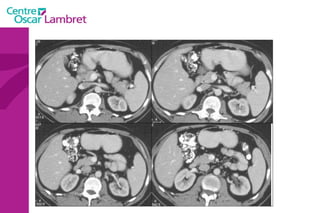

PIEGES Nodule hépatique

PIEGES Hernie Hiatale   Néoplasie